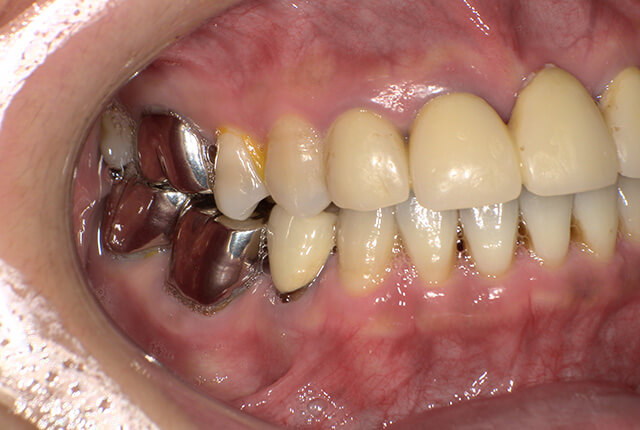

| 主訴 | 噛めない、食事がしっかりできる様になりたい。 |

| 診査診断 | 歯周病、歯の崩壊、不良補綴。 全顎的咬合異常、前歯の噛み合わせ、奥歯の噛み合わせに問題あり。 |

| 治療計画 | 欠損部インプラント 不良補綴のやり直しと欠損部インプラント。 咬合の再構築、なるべく歯を残せる様に治療計画を立案。 |

| 治療期間 | 6ヶ月 |

| 費用 | 290万円 |

| リスク | 一般的なインプラントのリスク、抜歯のリスク |